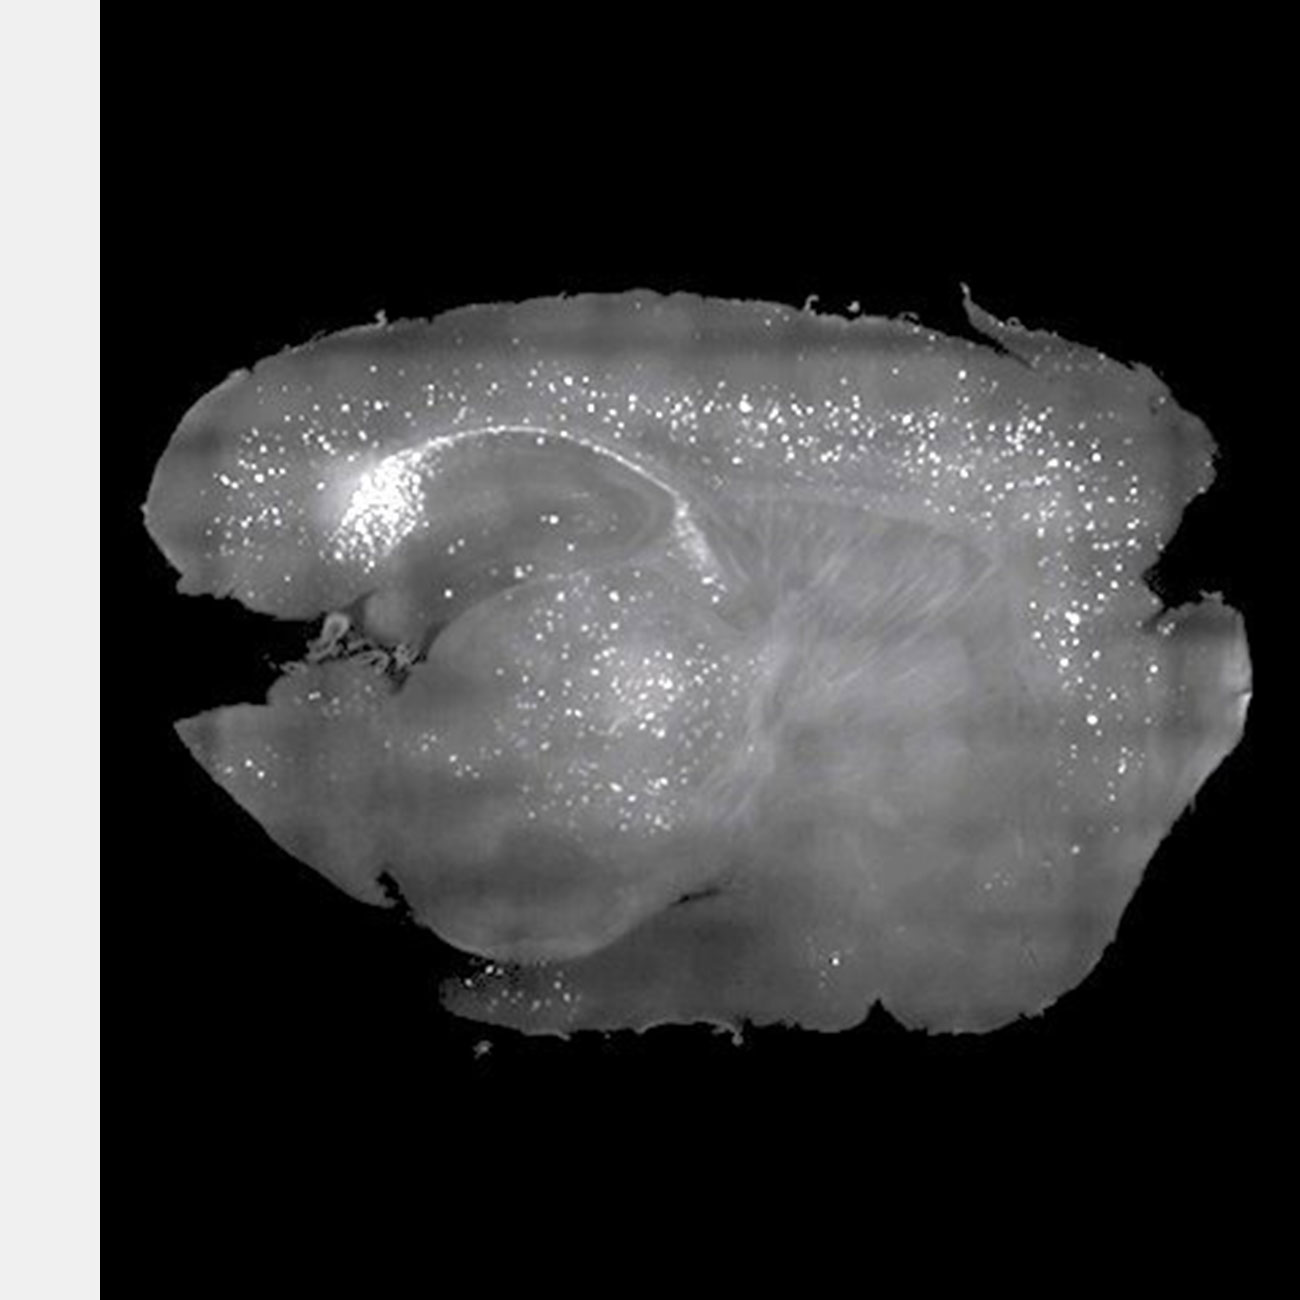

Амилоидные бляшки, которые мешают работе мозга мышей, удалили с помощью звуков. В будущем эти опыты могут привести к появлению дешевого и безлекарственного способа лечения нескольких форм деменции.